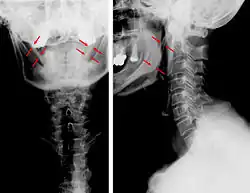

Anteroposterior and lateral radiographs of cervical spine showing ossification of the stylohyoid ligament on both sides |

Eagle syndrome (also termed stylohyoid syndrome,[1] styloid syndrome,[2] stylalgia,[3] styloid-stylohyoid syndrome,[2] or styloid–carotid artery syndrome)[4] is an uncommon condition commonly characterized but not limited to sudden, sharp nerve-like pain in the jaw bone and joint, back of the throat, and base of the tongue, triggered by swallowing, moving the jaw, or turning the neck.[1] First described by American otorhinolaryngologist Watt Weems Eagle in 1937,[5] the condition is caused by an elongated or misshapen styloid process (the slender, pointed piece of bone just below the ear) and/or calcification of the stylohyoid ligament, either of which interferes with the functioning of neighboring regions in the body, such as the glossopharyngeal nerve.[5]